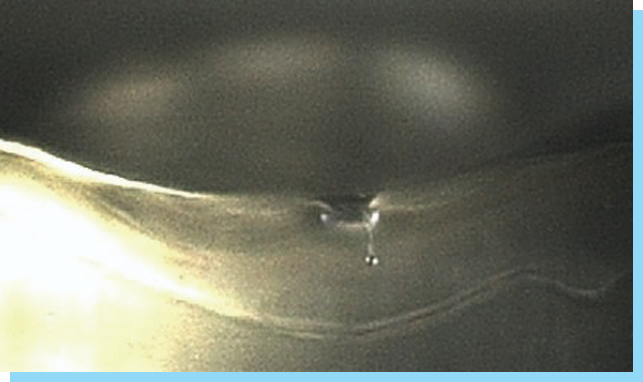

STEP 2

혈관 및 조직 수축으로

혈관 및 조직 수축으로

출혈, 멍, 붓기감소

-

[ 일반 리프팅 시술 후 바늘 자국 ]

-